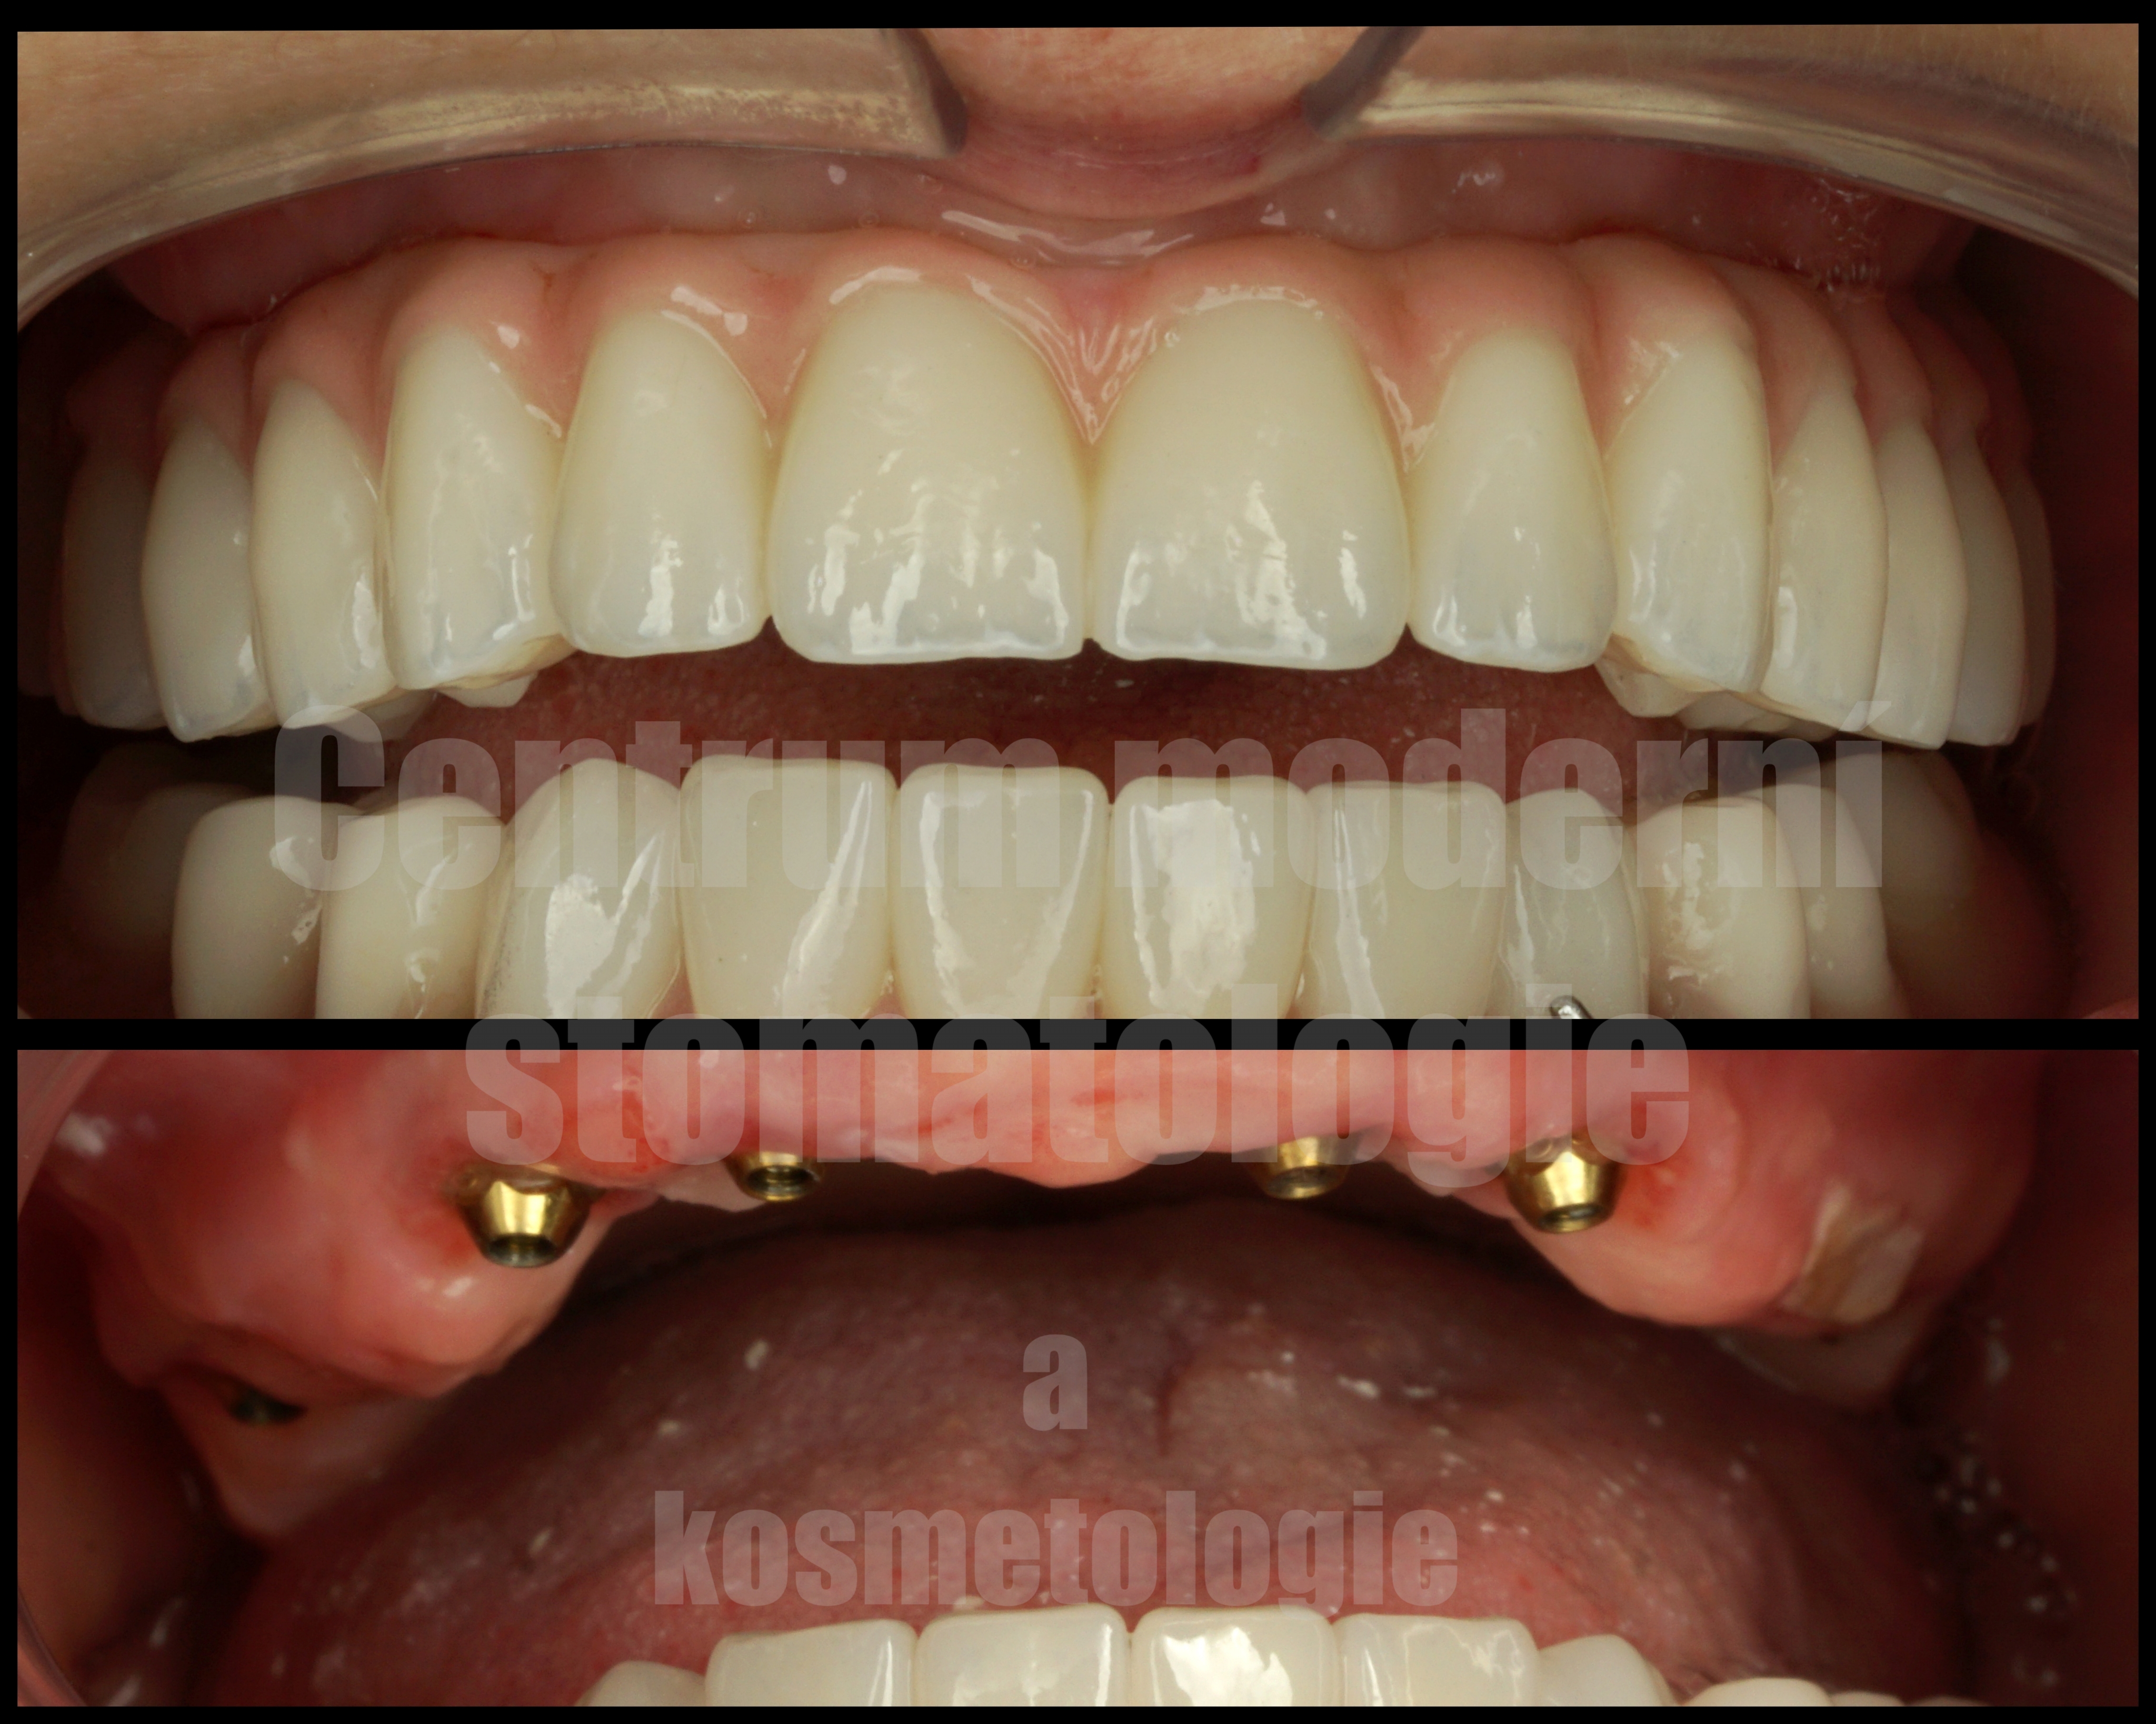

All-on-6 je moderní způsob náhrady celého zubního oblouku pomocí šesti implantátů, na kterých je upevněna fixní protetická práce.

Cílem ošetření All-on-6 je obnovit estetiku úsměvu, jistotu při kousání a komfort při každodenním fungování. Vhodnost tohoto postupu závisí na anatomii čelisti, kvalitě kosti, skusu a celkovém léčebném plánu.

Po implantaci následuje hojení. Za vhodných podmínek je v některých případech možné provést dočasné zatížení protetickou náhradou v krátkém čase po zákroku. Definitivní práce se zhotovuje po stabilizaci a vhojení implantátů.

• pevná náhrada celého oblouku,

• vyšší komfort oproti snímatelné náhradě,

• stabilní opora při kousání a mluvení,

• obnovení funkce a estetiky chrupu,